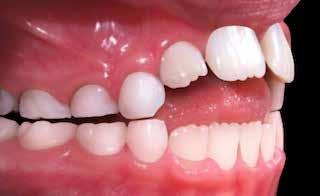

55 54 ESTETICA FUNZIONE POSTURA Valori cefalometrici ad 1 anno di terapia : ANB ANB 3,8 Posizione del Mascellare SNA 91.40 Posizione della Mandibola SNB 87,60 Angolo Articolare SArGo 155,00 Angolo Goniaco ArGoMe 122,00 Angolo incisivo inf^Corpo madibolare IiMand 80,20 Angolo incisivo Sup^Base Cranica Ant. IsCran 111,05 Angolo Interincisivo II 138,00 72, 73 _ Over-bite e over-jet. 74 _ Immagine laterale destra. 75 _ Immagine laterale sinistra. Considerazioni > La terapia precoce di tali malocclusioni è di primaria importanza in quanto impedisce la formazione di malocclu-

Dall’esame clinico si evince la III Classe dentale, l’inversione anteriore e l’over-jet negativo.

Presentazione del caso > F.V, bambino di cinque anni, presenta una malocclusione di II Classe scheletrica, III Classe dentale molare e canina destra e sinistra, morso inverso anteriore. Le arcate dentali mostrano usura degli elementi dentari anteriori a causa dell’occlusione patologica. Le linee mediane, superiore ed inferiore, sono centrate; il frenulo labiale superiore patologico per un’eccessiva estensione inter-incisale.

Il piano di trattamento prevede l’utilizzo di un dispositivo elastodontico di III Classe, da portare per due ore diurne e tutte le notti in modo passivo, senza effettuare alcun esercizio, al fine di ripristinare una relazione molare e canina bilaterale di I Classe ed il corretto avanzamento maxillare e inibire l’eccessiva crescita mandibolare. È possibile ottenere il risultato in pochissimi mesi di terapia, essendo la crescita del paziente molto attiva.